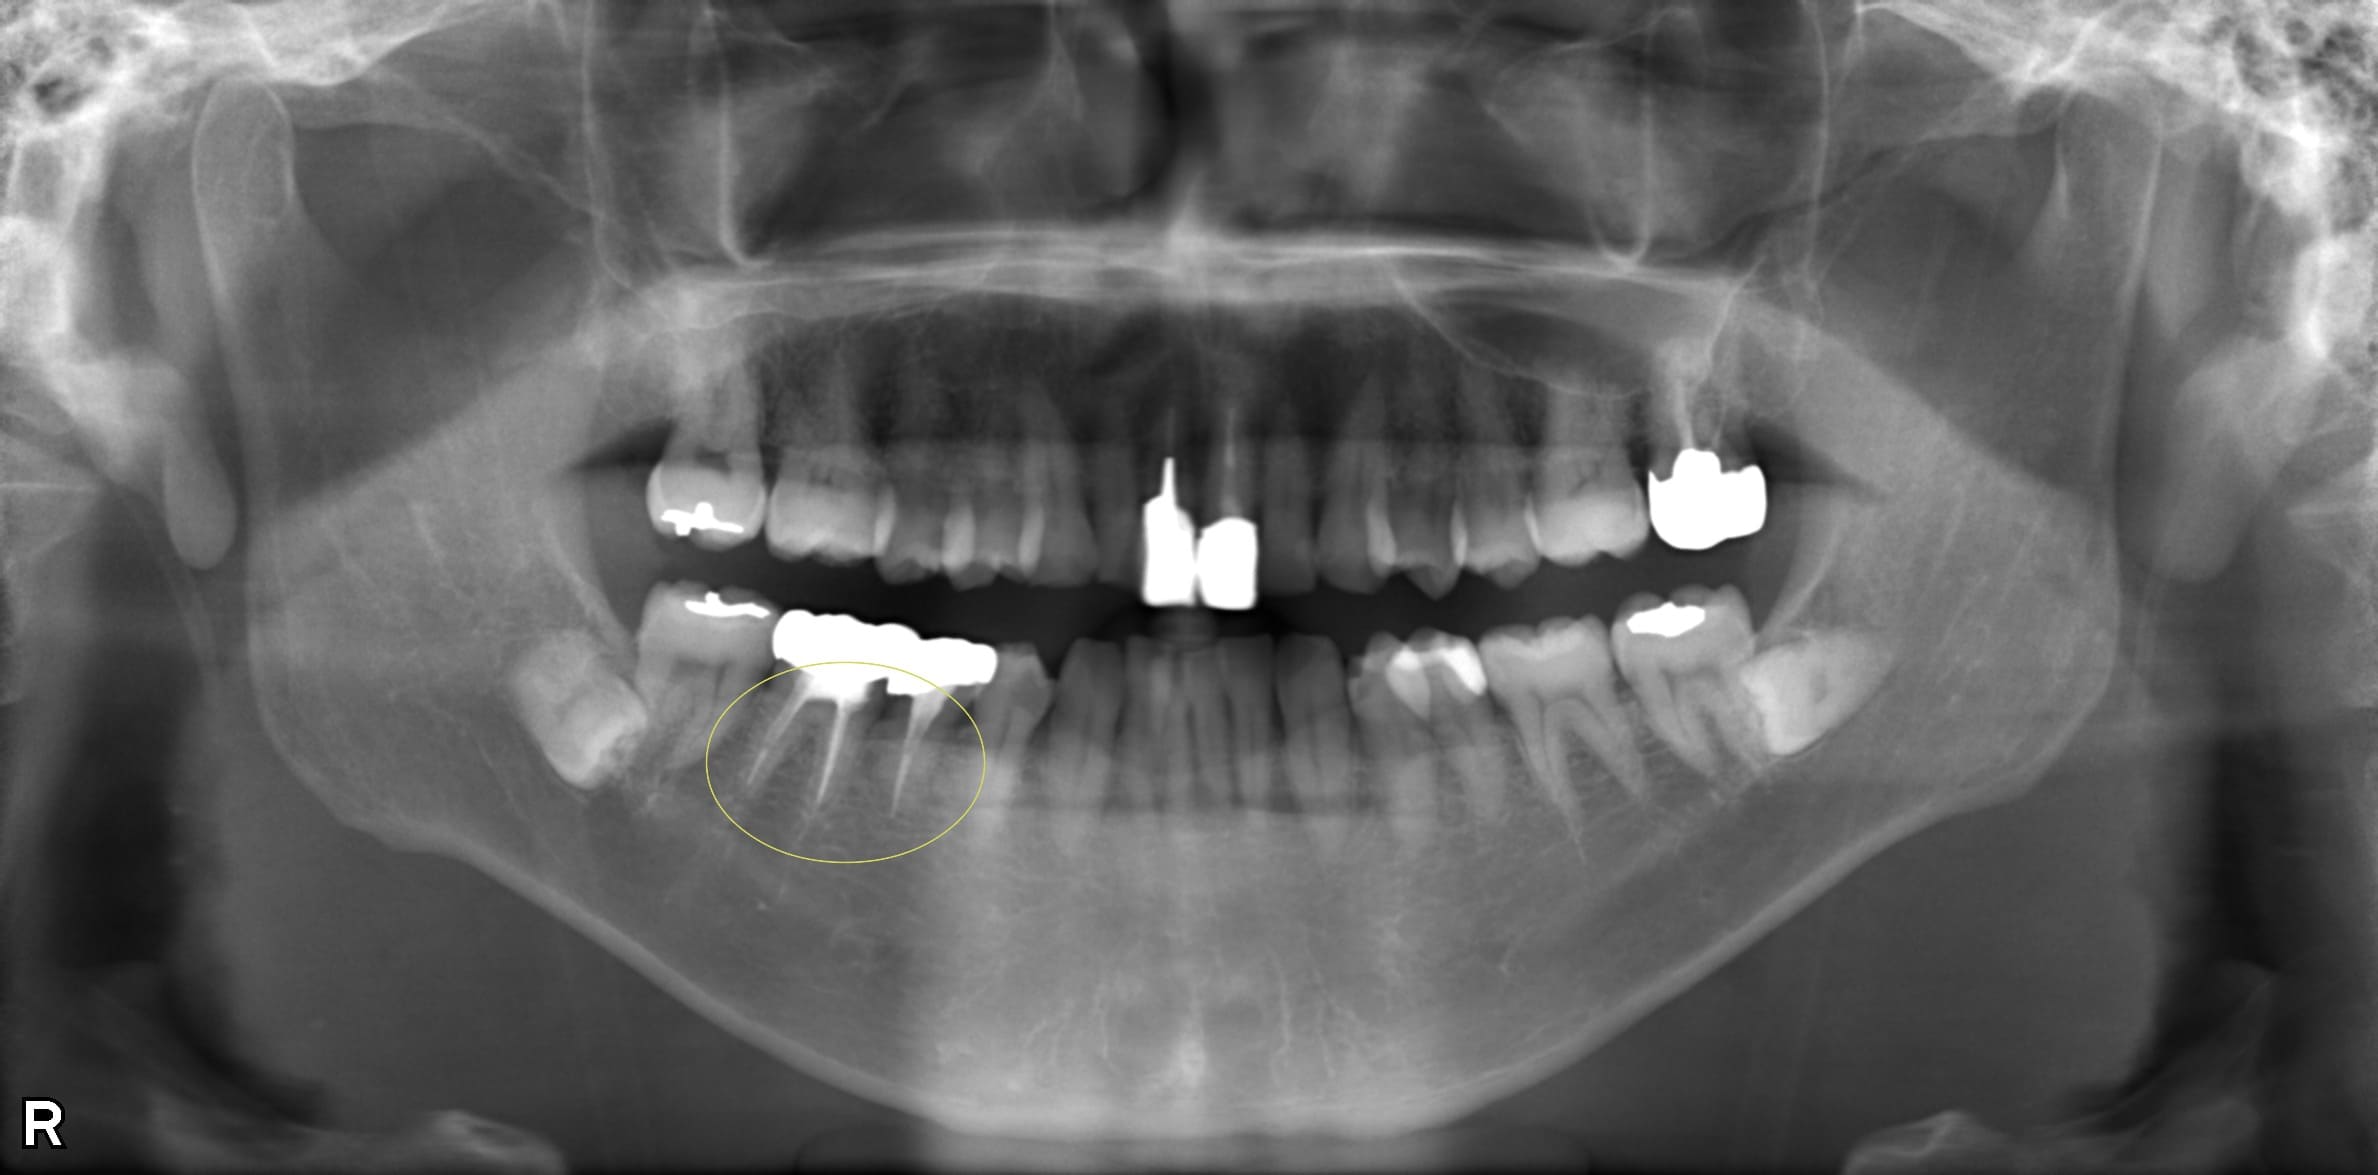

- 大人の矯正ブログ歯並びがガタついていて、かなり内側に生えてしまっている悩みで来院されたT.Kさんからの相談